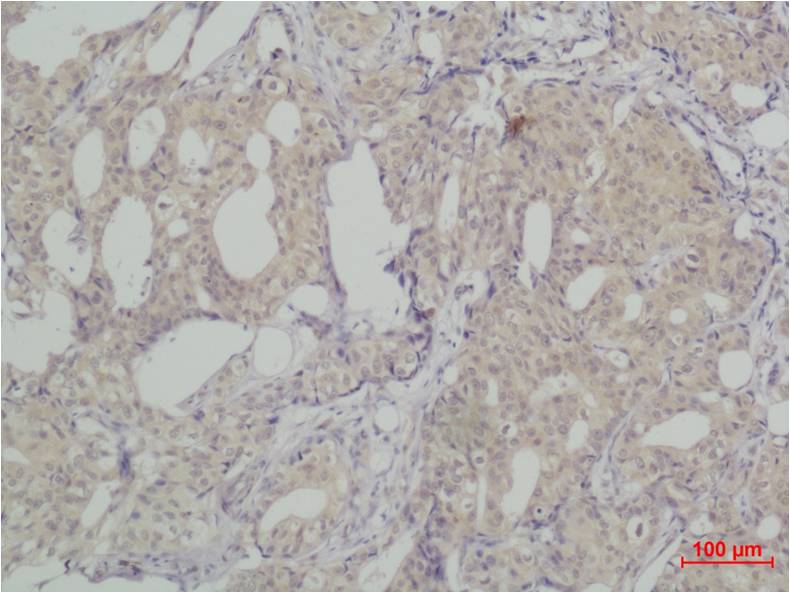

Immunohistochemical analysis of paraffin-embedded human Breast caricnoma using SLUG(EA168)Rabbit pAb diluted at 1:500.